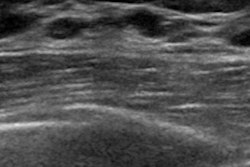

Virginia Tech Carilion School of Medicine in Roanoke has debuted ultrasound technology for the classroom that consists of portable machines outfitted with 12-lead electrocardiogram technology.

The devices allow students to view images of the heart as they measure electrical activity through the electrodes attached to a subject's body, according to the school.

Carilion School of Medicine said it is one of only a few to have a designated ultrasound curriculum. First-year students learn to identify basic anatomical structures, while second-year students learn to identify pathology.